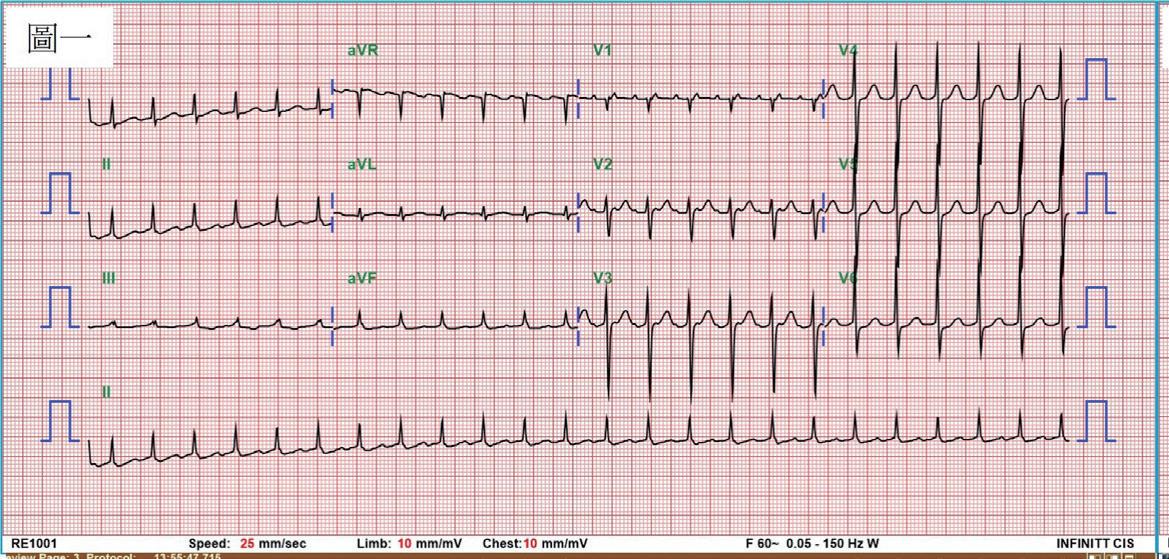

一位 76 歲女性,有高血壓以及陣發性心房顫動病史,規律於心臟科門診服用抗心律不整藥物 (flecainide) 以 及抗凝血劑 (apixaban) 以控制慢性病。然而,病人最近數月來感到間歇性胸悶與心悸,且症狀逐漸加重。經血 管介入專家排除冠狀動脈狹窄阻塞之問題後,判斷此病人之不適與多種嚴重心律不整有關 ( 如圖一與圖二 ) ,包 含可能源自於左心房的心房撲動 (atypical atrial flutters) 。經詳細解釋與討論,病人決定入院接受電氣生理檢查 與電氣燒灼治療。術前電腦斷層顯示左心房及左心耳無血栓,左心房有擴大 ( 約為 160 毫升 ) 。手術當日,病人心 律為 counter-clockwise isthmus-dependent atrial flutter( 如圖三 ) ,利用 entrainment method ,冠狀竇近端比遠端更 近 flutter circuit , 3 維傳播路徑圖為逆時針旋轉路徑。但是在 cavo-tricuspid isthmus 阻斷後, flutter 並未停止,發 生了訊號序列以及 cycle length 的變化,此時右側心房沒有辦法找到合適 entrainment 位置,經兩心房 3 維傳播路 徑圖判定病人之心律不整已轉變為源自左心房後壁之 atypical atrial flutter ,但是在左心房後壁阻斷後, flutter circuit 和 cycle length 仍不斷改變。在左心房經歷如同警匪追逐戰一般的多次阻斷以及訊號序列轉變後 ( 如圖四至 圖六 ) ,終於在冠狀竇 (coronary sinus) 遠端完成此病人的心律不整電氣燒灼手術 ( 如圖七 ) ,且無法再誘發。此病 人之心房撲動訊號序列變化與燒灼相關整理如圖八。術後病人恢復良好,胸悶心悸感已完全消除,固定於門診 領取抗凝血劑與低劑量抗心律不整藥物持續服用併追蹤。

(圖一)、 病人臨床上偵測到的第一種心房撲動,雖然下壁導極有鋸齒狀之表現 (saw-tooth appearance), 但細看可發現其特徵並不是典型之表現。搭配V1導極之正向波,可能仍是一種源自左心房之 atypical atrial flutter?

(圖二)、 病人臨床上偵測到的第二種心房撲動,心房之cycle length較第一種心房撲動略慢。下壁導極沒 有典型之鋸齒狀特徵,而且V1導極是正向波,應為一種源自左心房的atypical atrial flutter。

(圖三)、

病人接受電氣燒灼手術當天的 baseline rhythm 。為一個 counter-clockwise atrial flutter。透過entrainment method得知冠狀 竇近端較冠狀竇遠端更靠近flutter circuit。